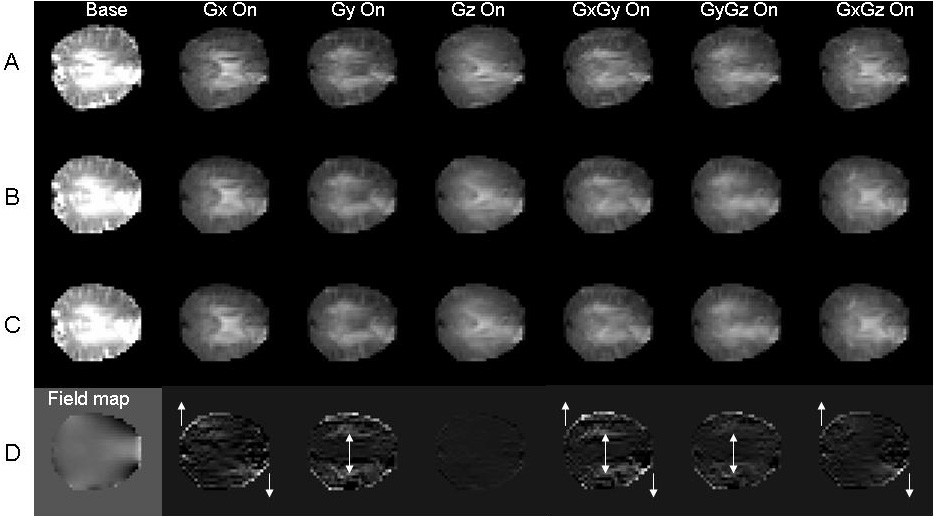

Figure: A) DTI dataset containing one base image and six diffusion weighted images. B) DTI dataset after geometric correction using B0 field map only. C) DTI dataset after the full correction procedure using B0 field map and eddy current gradient field maps. D) The difference images between C (full correction) and B (B0 correction only). The corresponding shearing and scaling effects due to eddy currents are indicated by arrows. The first column shows the B0 field map.

- Diffusion tensor imaging (DTI) has seen increased usage in clinical and basic science research in the past decade. By assessing the water diffusion anisotropy within the biological tissue, e.g. brain, researchers can infer different fiber structures important for neural pathways. A typical DTI dataset contains at least one base image and six diffusion weighted images along non-collinear encoding directions. The resultant images can then be combined to derive the three principle axes of the diffusion tensor and their respective cross terms, which can in turn be used to compute fraction anisotropy (FA) maps, apparent diffusion coefficient (ADC) maps, and to construct axonal fibers.

- The above operations all assume that DTI images along different encoding directions for the same brain register to each other without spatial distortions. This assumption is general false, as the large diffusion weighting gradients would usually induce eddy currents to generate encoding-direction dependent field gradients, leading to mis-registration within the DTI dataset. Traditional methods for correcting magnetic field induced distortions do not usually take into account these direction-dependent eddy currents unique for DTI, and they are usually time consuming because multiple phase images need to be acquired.

- The theory and implementation of a fast, efficient and effective method to correct for the main field and eddy current-induced direction-dependent distortions for DTI images under a unified frame to facilitate the daily practice of DTI acquisitions have been reported (see References below).